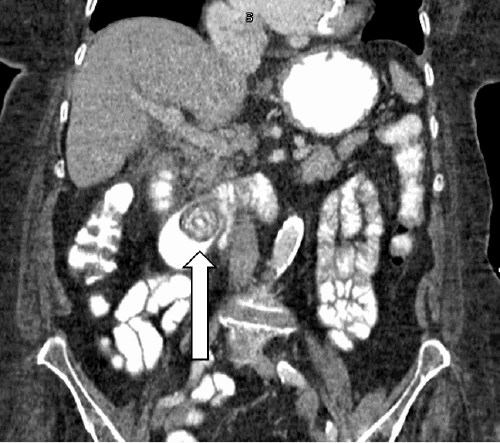

On examination, she exhibited tachycardia and clinical signs of dehydration, though without overt evidence of peritonitis. An abdominal ultrasound demonstrated a mildly dilated extrahepatic biliary duct, measuring 12 mm in diameter. The cholecystostomy tube appeared dislodged and was causing local pain, leading to its removal by the emergency physician. Subsequent computed tomography (CT) imaging of the abdomen and pelvis with oral and intravenous contrast revealed a 2.7 cm calcified gallstone impacted in the proximal duodenum. Associated findings included mucosal edema proximal to the impaction site, significant gastric distension, and pneumobilia, collectively consistent with Rigler’s triad and indicative of a gallstone-induced obstruction (Figure 1).

Figure 1. Contrast-enhanced CT of Calcified Stone at Proximal Duodenum. Published with Permission

Our patient exhibited several classic features of Bouveret syndrome, including advanced age (>75 years), nausea, vomiting, abdominal pain, tachycardia, and gastric distension. The abdominal and pelvic CT scan with intravenous contrast clearly demonstrated Rigler’s triad: an ectopic gallstone impacted in the duodenum, significant gastric distension with proximal duodenal mucosal edema, and pneumobilia (Figure 1).7